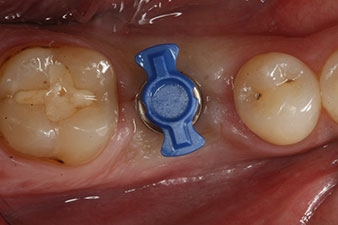

SmartPeg

Fig. 4: SmartPeg measuring posts screwed on to measure the implant stability quotients with the integrated W&H Osstell ISQ module.

The torque used for the machine-driven placement was 43 Ncm. In addition, after screwing a measuring post (SmartPeg) specially matched to the implant, the ISQ value was measured with the probe of the W&H Osstell ISQ module.

This module is an optional extra for the W&H Implantmed and is docked to the implantology motor (see Fig. 11). The dimensionless ISQ value immediately after insertion was 64 orovestibular and 68 mesiodistal (maximum value = 100).